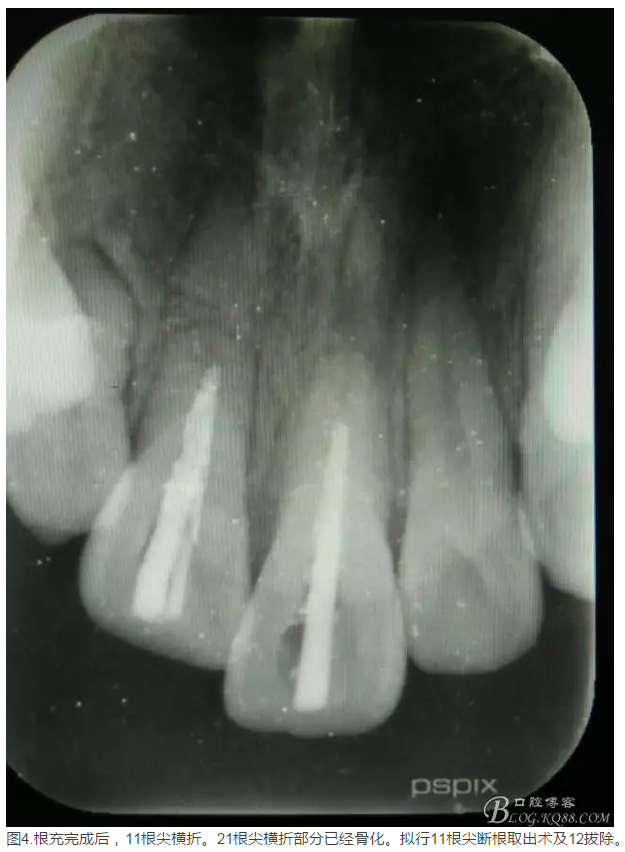

患者、李xx、男、15歲,主訴:牙不齊,矯正牙齒。??茩z查:發(fā)現(xiàn)11、21根尖三分之一折斷,患者否認有外傷史。正畸科治療建議如圖1.。術(shù)前簽手術(shù)同意書。